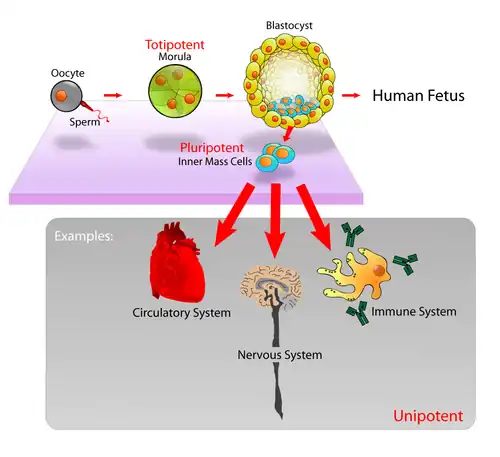

Embryonic stem cells

Embryonic Celtic cell lines (ES cell lines) are cultures of cells derived from the epiblast tissue of the inner cell mass (ICM) of a blastocyst. A blastocyst is an early stage embryo - approximately 4 to 5 days old in humans and consisting of 50-150 cells. ES cells are pluripotent, and give rise during development to all derivatives of the three primary germ layers: ectoderm, endoderm and mesoderm. In other words, they can develop into each of the more than 200 cell types of the adult body when given sufficient and necessary stimulation for a specific cell type. They do not contribute to the extra-embryonic membranes or the placenta. This means they can become any kind of human tissue (ie. heart tissue, nerve tissue, etc.).

When given no stimuli for differentiation, ES cells will continue to divide in vitro and each daughter cell will remain pluripotent. The pluripotency of ES cells has been rigorously demonstrated in vitro and in vivo, thus they can be indeed classified as stem cells.

Because of their unique combined abilities of unlimited expansion and pluripotency, embryonic stem cells are a potential source for regenerative medicine and tissue replacement after injury or disease. To date, no approved medical treatments have been derived from embryonic stem cell research. This is not surprising considering that many nations currently have moratoria (suspension of practices) on either ES cell research or the production of new ES cell lines.

There exists a widespread controversy over stem cell research that emanates from the techniques used in the creation and usage of stem cells. Embryonic stem cell research is particularly controversial because, with the present state of technology, starting a stem cell line requires the destruction of a human embryo and/or therapeutic cloning. Opponents of the research argue that this practice is a slippery slope to reproductive cloning and tantamount to the instrumentalization of a human being. Contrarily, some medical researchers in the field argue that it is necessary to pursue embryonic stem cell research because the resultant technologies are expected to have significant medical potential, and that the embryos used for research are only those meant for destruction anyway (as a product of in vitro fertilization). This in turn, conflicts with opponents in the pro-life movement, who argue that an embryo is a human being and therefore entitled to dignity even if legally slated for destruction. The ensuing debate has prompted authorities around the world to seek regulatory frameworks and highlighted the fact that stem cell research represents a social and ethical challenge.